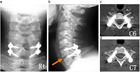

1. 頭蓋頚椎、頚胸椎、胸腰椎の各移行部での脊椎損傷は他の臓器との重なりが多く、単純X線では見落とされることがあり、CTによる評価が推奨される。

1. 高齢化に伴い強直性脊柱や骨粗鬆症を基盤とした脊椎損傷の比率が上昇しており、その病態、損傷形態に応じた治療法、手術法が求められる[1]